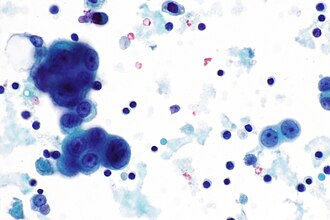

Adenocarcinoma

Cytology

Adenocarcinoma in fluid - features:[11]

- Classically large morules (clusters of cells that are heaped/are "3-dimensional"), known as cannonballs, with "community borders".

- "Community border" = smooth, low surface area border; should be differentiated from a "knobby" border seen in mesothelioma.

Images

Case 1

Adenocarcinoma - high mag. (WC)